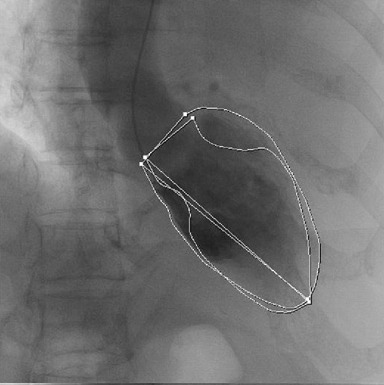

緊急冠動脈造影検査を施行したが、左右の冠動脈に狭窄病変はなく(図2、図3)、左室造影検査にて前壁から心尖部にかけて壁運動はほとんど消失、心基部のみが収縮しており(図4)、「たこつぼ心筋症」と診断された。

図4